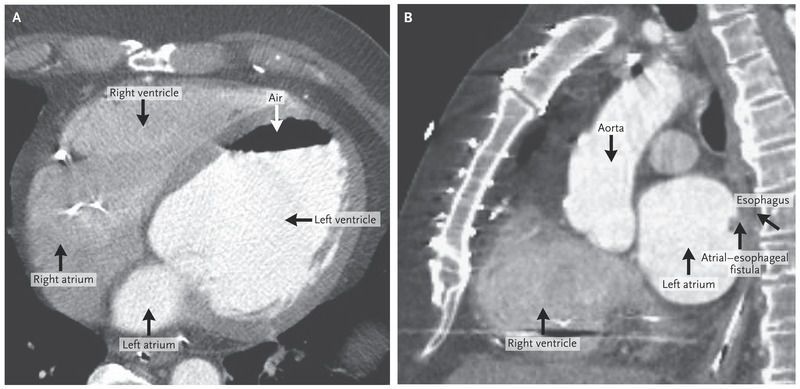

A 60-year-old man with coronary artery disease, ischemic cardiomyopathy with biventricular implantable cardioverter–defibrillator placement, and atrial fibrillation presented with chest pain and numbness in both arms. During his initial presentation, he suddenly collapsed and became unresponsive. Computed tomographic (CT) angiography of his chest, abdomen, and pelvis was performed to evaluate the possibility of aortic dissection. The images showed gas in the left ventricle (Panel A). Further review revealed gas in the left atrium with a connection to the esophagus (Panel B). His family later reported that he had undergone radiofrequency ablation for atrial fibrillation 6 weeks earlier. The gas in the heart was thought to be from an atrial–esophageal fistula that may have developed after this procedure. Imaging also showed renal infarcts, probably from air emboli. Findings from brain imaging were unremarkable, but the patient remained without notable neurologic function. His family elected against surgery, given his poor prognosis. The patient died a few hours after his initial presentation. An atrial–esophageal fistula can be a complication of radiofrequency ablation and is associated with a substantial risk of death. Chest CT is the preferred diagnostic test for this condition; transesophageal echocardiography should be avoided because intubating the esophagus can cause further gas embolization.